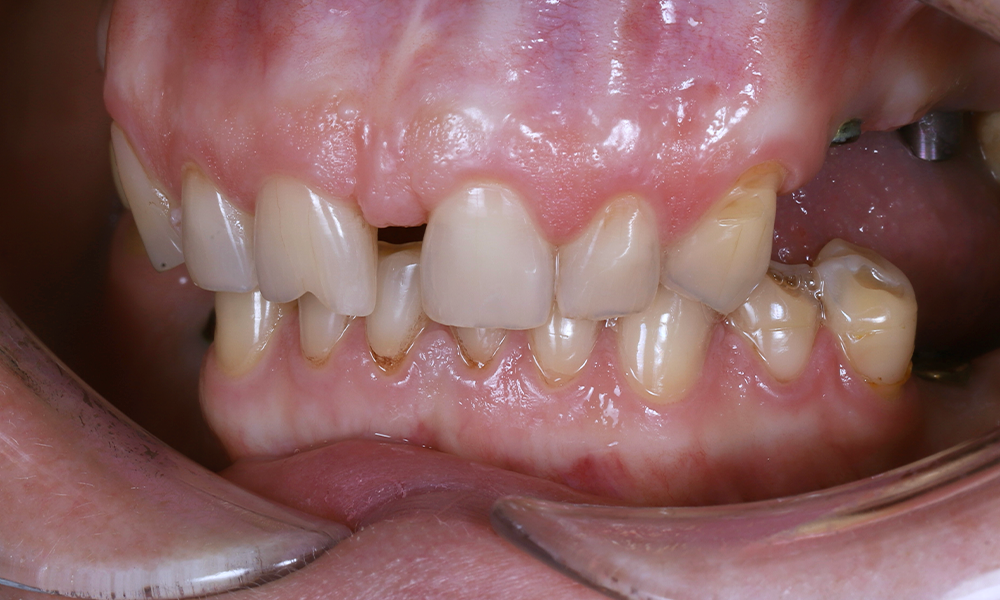

До

Какая ситуация была изначально?

- У пациентки отсутствовали боковые зубы.

- Была выраженная диастема — заметный промежуток между передними резцами.

- Стираемость зубов.